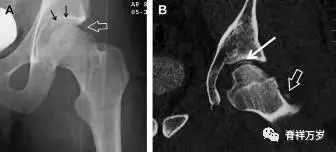

股骨颈应力性骨折

股骨颈应力性骨折在参加耐力运动的运动员中常见,且常发生在股骨颈压力侧。股骨颈基底部发现一垂直于骨皮质的线性硬化带可诊断这种类型的疲劳性骨折(图 7)。

图 7 长跑运动员股骨颈应力性骨折。X 片(A)和冠状位 CT 多维重建(B)图像示穿过股骨颈内侧皮质中的透亮区(箭头),周围硬化。骨折垂直于皮质